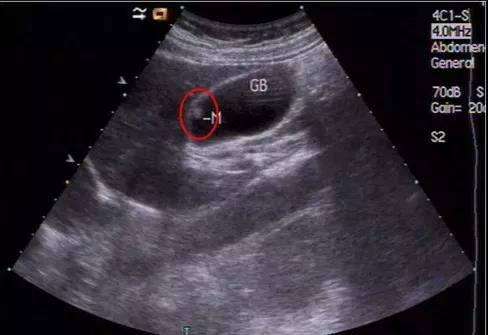

3、無蒂息肉(包括膽囊壁增厚>4毫米);

①看真假:真正可能變癌的是真息肉,假息肉不用管;

②看大?。?/strong>長到1厘米了就需要考慮手術,風險大了;